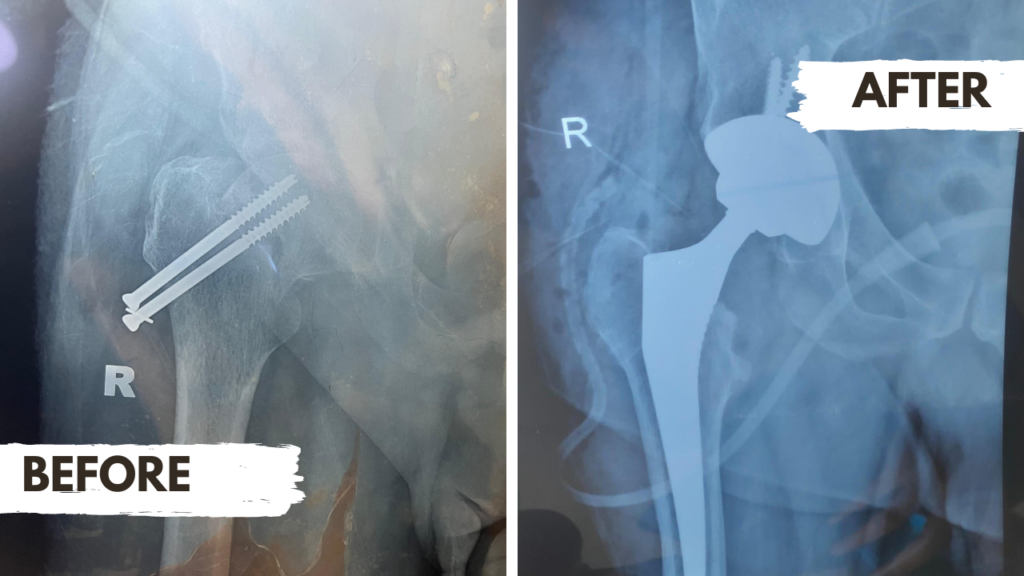

Joint Replacement (Arthoplasties)

Arthroplasty is a medical procedure that involves the surgical reconstruction or replacement of a damaged joint. This operation is typically performed when chronic pain, stiffness, and mobility limitations significantly impact a patient’s quality of life. Joint replacement surgeries can be performed on various joints, including knees, hips, and shoulders. To achieve the best possible outcomes, arthroplasty is often performed by highly trained and experienced orthopedic surgeons who specialize in joint reconstruction.

These specialists use advanced surgical techniques and medical technologies to ensure that the surgery is as precise and minimally invasive as possible. Patients who undergo arthroplasty can expect a significant improvement in their joint function and a reduction in pain, allowing them to return to everyday activities more easily. If you are considering joint replacement surgery or have any questions about this procedure, consult with a qualified orthopedic surgeon to learn more.